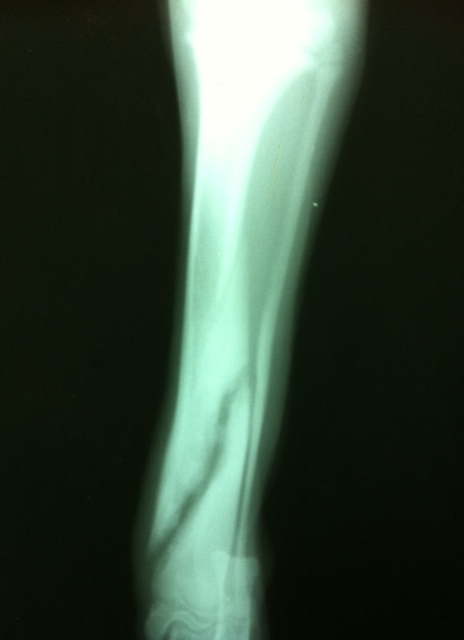

Rumba acude a consulta para hacer un seguimiento. Lo primero que me sorprende es que no paraba quieta, estaba todo el tiempo jugando, la extremidad no estaba nada inflamada . Los dueños dijeron que al segundo día de tratamiento dejaron el Meloxican ( analgésico , antiinflamatorio) ya que empezaba a apoyar la pata. Es decir, Rumba estaba tomando sólo el tratamiento homeopático y su carácter era de juego, dormía perfectamente y su extremidad con una triple fractura de tibia no estaba inflamada (increíble). Se repite la radiografía en la cual valoramos la correcta alineación y donde se observa que no hay inflamación.